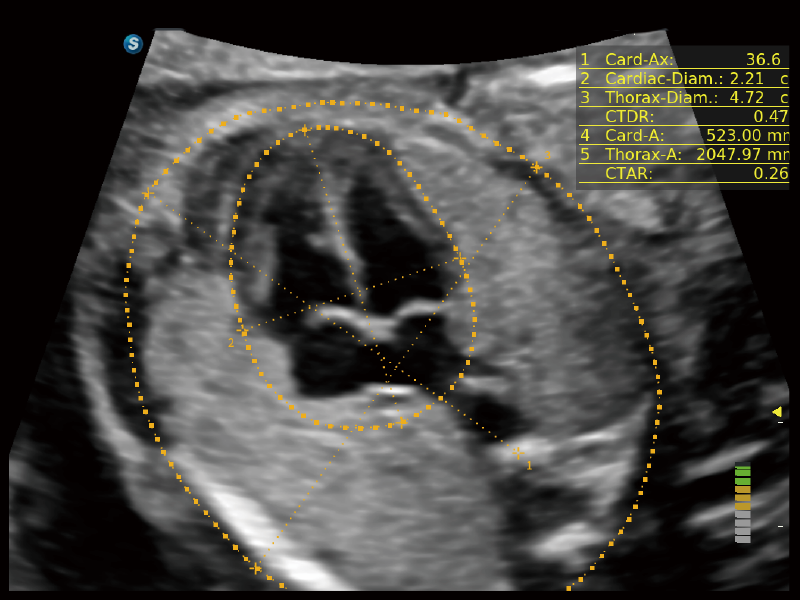

作為開立醫(yī)療全新打造的超高端旗艦超聲產(chǎn)品,從探頭抬起喚醒開啟掃查到多維探頭發(fā)射接收,通過先進(jìn)的場(chǎng)成像發(fā)射、自適應(yīng)聚合重建等技術(shù),基于RF Data原始射頻數(shù)據(jù)在圖像生成、高端功能等方面實(shí)現(xiàn)突破,為婦產(chǎn)科、兒科提供全方位臨床解決方案。

夢(mèng)溪?P80以“關(guān)愛女性”為基石,提供全方位的解決方案,量身定制以滿足女性的健康需求,涵蓋婦科、生殖健康檢查、產(chǎn)前篩查及產(chǎn)后康復(fù)等領(lǐng)域。